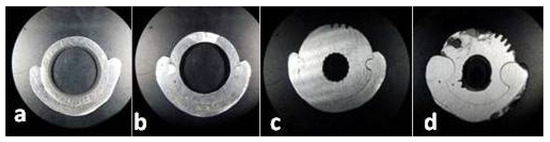

Figure 11. Sections through the framework assemble: (a) A1; (b) A2; (c) A3; (d) A4.

After the initial coupling, the joint surfaces between the two hybrid frameworks of the dental prosthetic frameworks assembles were mechanically machined to obtain a mirror-like texture, following the cutting of the other sections to obtain the areas A2, A3, A4, and to finish the area A1.

The following horizontal sections were made: one at the supra-cervical level (resulting the surfaces I1 and A1), one at the middle level (resulting the surfaces A2 and A3), and one straightening the occlusal (upper) surface (resulting the surface A4); between all sections, there were 2 mm in vertical plane.

All sections (Figure 10) were made by rotary cutting using a 0.5 mm silicon carbide (SiC) disc at a speed of 15,000 rpm and then finished with sandpaper (500, 1200) (Figure 11).

A total of 500 measured lengths were analyzed, five lengths for each of the 100 microscopic segments and four areas of horizontal sections (A1, A2, A3, and A4), (Figure 10 and Figure 11).